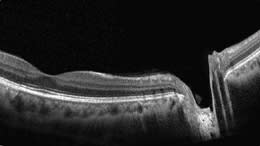

MAIN IMAGE ADAPTED FROM RETINAL OCT; DIGITAL ILLUSTRATION BY JOEL & SHARON HARRIS. INSET IMAGES DEPICT POST-LASIK CORNEA (TOP) AND NARROW ANGLE (BOTTOM), COURTESY OF DAVID HUANG, MD, DOHENY EYE INSTITUTE, LOS ANGELES.

FD-OCT provides highly detailed images of anterior (left) and posterior (right) structures. RTVue scans courtesy of David Huang, M.D.